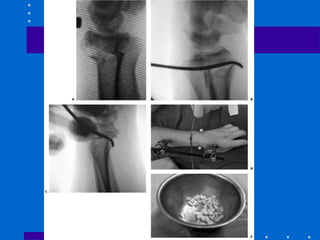

Pinagem e gesso

• 1º estilóide 2º coluna intemediária (fossa

lunar) de dorsal ulnar para proximal radial

3º fragmentos impactados podem ser

suportados por fios subcondrais transversais

Kapandji

• Fios intrafocais radial e dorsal servindo de

suporte

• Original 1 fio dorsal e 1 estilóide

• Modificada: 2 fios dorsais e 1 estilóide

• Tendência a translação do fragmento distal

• Efetivo para fraturas extra-articulares